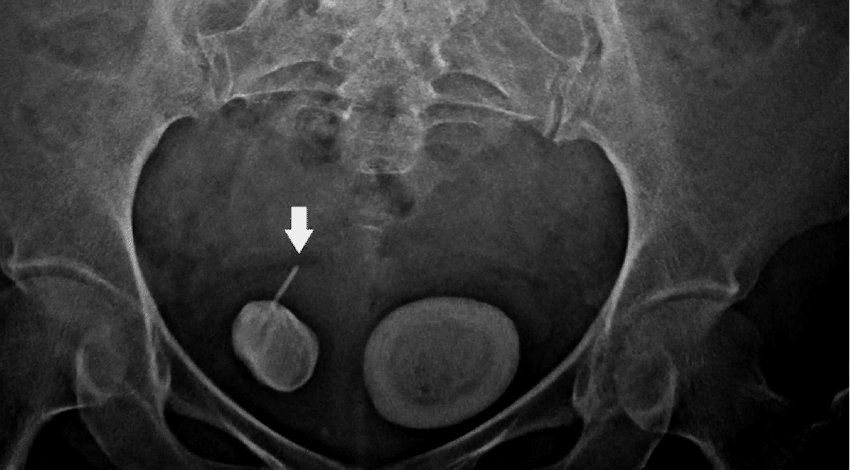

La radiografía renal y vesical utiliza una dosis pequeña de radiación para producir imágenes en distintas partes del sistema urinario. Este procedimiento se practica frecuentemente para diagnosticar cálculos renales.

Se trata de un procedimiento rápido, que no produce dolor y que no requiere ninguna preparación especial.

Por lo general, una radiografía renal y vesical no tarda más de 15 minutos y en ella participa un médico radiólogo, además de personal de enfermería